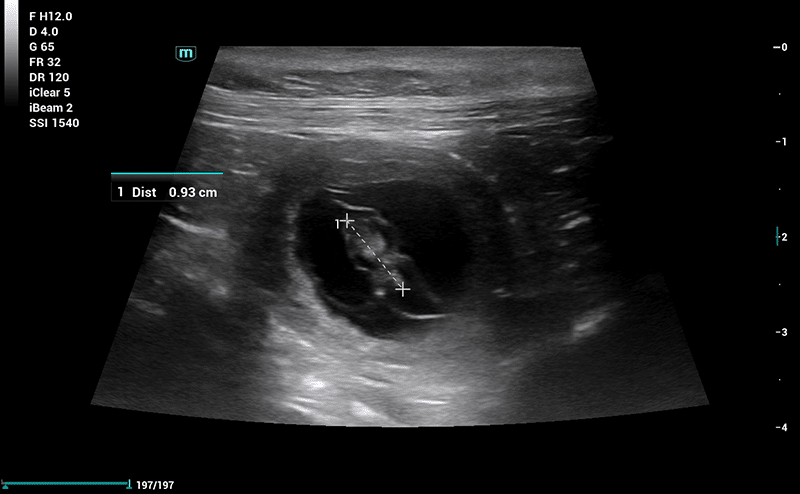

Drægtighedsscanning

Drægtighedsscanning anbefales omkring dag 24-26. Her vil vi dels kunne konstatere drægtighed, men også kigge på fostrenes udviklingstrin og hjerteslag, samt komme med et estimat på antal fostre.​

Kraniemål kan benyttes til fastsættelse af fødselstermin hos både hunde og katte.